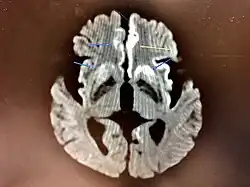

The symptoms of CJD are caused by the progressive death of the brain's nerve cells, which are associated with the build-up of abnormal prion proteins forming in the brain. When brain tissue from a person with CJD is examined under a microscope, many tiny holes can be seen where the nerve cells have died. Parts of the brain may resemble a sponge where the prions were infecting the areas of the brain.[20]

The classic histologic appearance is spongiform change in the gray matter: the presence of many round vacuoles from one to 50 micrometers in the neuropil, in all six cortical layers in the cerebral cortex, or with diffuse involvement of the cerebellar molecular layer.[59] These vacuoles appear glassy or eosinophilic and may coalesce. Neuronal loss and gliosis are also seen.[60] Plaques of amyloid-like material can be seen in the neocortex in some cases of CJD.[61]

However, extra-neuronal vacuolization can also be seen in other disease states. Diffuse cortical vacuolization occurs in Alzheimer's disease, and superficial cortical vacuolization occurs in ischemia and frontotemporal dementia. These vacuoles appear clear and punched out. Larger vacuoles encircling neurons, vessels, and glia are a possible processing artifact.[58]